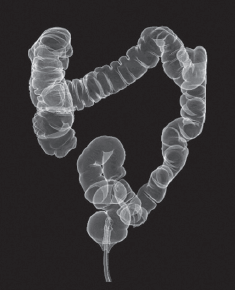

이중바륨 대장 조영술

항문을 통해 작은 튜브를 삽입하고 바륨이라는 조영제와 공기를 넣고 대장 내부를 공기로 확장시킨 다음, 대장 속의 대장 점막에 이상이 있는지 검사하는 방법입니다. 검사 중 진통제나 수면유도제가 필요치 않으며 전체 대장을 안전하게 검사할 수 있다는 장점이 있는 반면, 정확한 검사를 위해 하제를 이용하여 장을 비우는 것이 필요하고 방사선 노출 위험이 있다는 단점이 있습니다. 무엇보다 작은 병변에 대해서 예민도가 대장 내시경 검사에 비해 낮아 작은 용종이나 암을 발견하지 못할 수 있습니다. 용종이나 암이 의심되는 경우 정확한 진단 및 조직검사를 위해 대장 내시경 검사를 추가로 받아야 합니다.